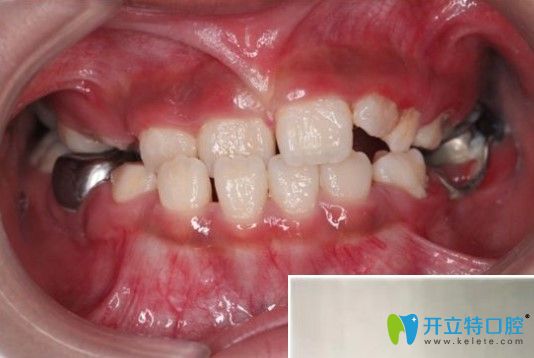

醫(yī)生給孩子檢查口腔時(shí)候拍的照片,特別認(rèn)真,動(dòng)作很輕柔▼

杭州兔牙醫(yī)醫(yī)生給孩子檢查口腔時(shí)候拍的照片

這是我家女兒的牙齒照,以前沒關(guān)注過▼

孩子地包天在凸牙醫(yī)做矯正前的牙齒圖